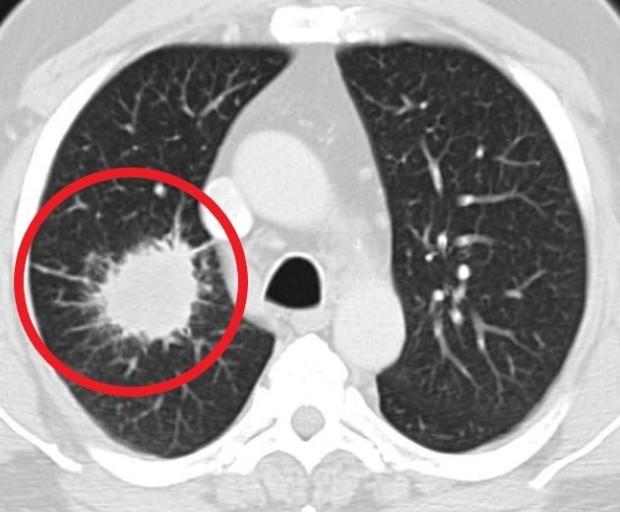

- 호흡 곤란 및 가슴 통증

- 설명: 폐렴의 가장 심각하고 중요한 증상입니다. 폐에 염증이 생겨 폐 기능이 떨어지면서 숨쉬기 힘들어지며, 얕고 빠른 호흡을 하게 됩니다. 심한 경우 가슴에 통증을 느끼거나, 옆구리가 결리는 듯한 느낌을 받을 수 있습니다.